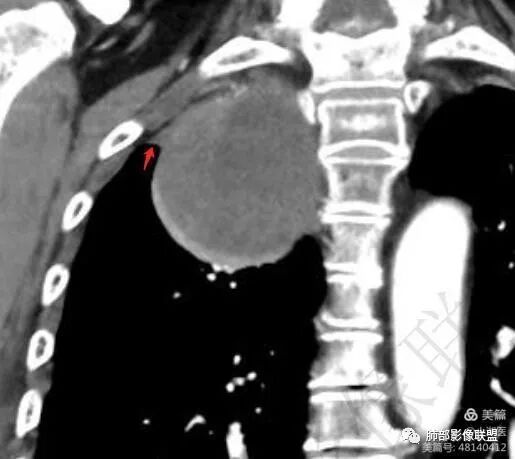

1. 右上胸廓入口区类椭圆形块影,边界清楚光整,纵向“嵌顿”于颈根部及上纵隔,向上推移右锁骨下动静脉,向外下方推移上肺胸膜及肺组织(肺血管、支气管),向前推移上腔静脉,界限清楚。

2. 块影不均匀轻度强化,可见较均匀实性区及液性密度区,未见积气、囊壁样结构、钙化或脂肪密度。可疑部分肋间动脉分支进入。

3.块影相邻椎骨及肋骨明确推压或骨质吸收破坏,未见椎管内结节或椎间孔扩大。

4.双肺门及纵隔未见肿大淋巴结。

综合分析:

1.块影定位肺外-上纵隔。块影密度以及强化方式不支持胸腔内甲状腺肿、副节瘤、巨淋巴结增生、支气管囊肿以及畸胎瘤等。

肿块部位、密度以及强化特点聚焦于良性神经鞘瘤及孤立性纤维瘤。

2.肿块远离胸膜向上延伸不大符合胸膜来源的孤立性纤维瘤。

3.而“A/B”区密度特点以及上下径较大更支持神经鞘瘤,尽管这不属于好发部位。